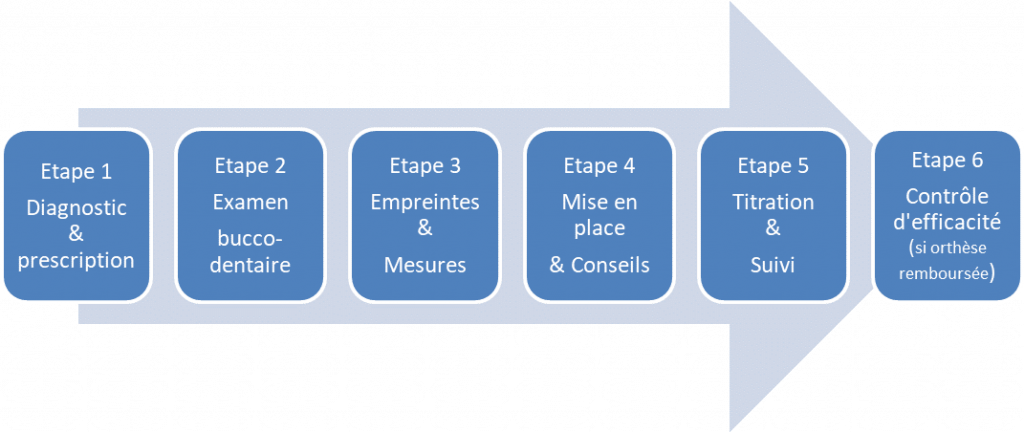

Les étapes pour obtenir votre orthèse TALI

- La première étape consiste à prendre rendez-vous avec un chirurgien-dentiste formé. Pour obtenir les coordonnées d’un professionnel formé il vous suffit de remplir le formulaire en cliquant-ici.

- Le dentiste va vérifier que votre état bucco-dentaire est bon. Il prendra ensuite vos empreintes et effectuera certaines mesures nécessaires à la confection de l’orthèse TALI.

- Nous récupérons ces éléments par coursier dans les 24h et fabriquons votre orthèse TALI dans un délai moyen de 15 jours.

- Votre dentiste effectuera la pose de votre orthèse et programmera 2 à 4 rendez-vous de réglages.

- Au cours de ces rendez-vous il optimisera l’efficacité et la tolérance du traitement jusqu’à obtenir le meilleur compromis confort/efficacité.

- Un rendez-vous de suivi tous les 6 mois doit ensuite être effectué.

Dans ce cas la procédure implique plusieurs étapes :

- Le médecin du sommeil ayant réalisé l’enregistrement doit remplir une Demande d’Entente Préalable (DEP).

- La DEP doit être envoyée au centre de sécurité sociale du patient. L’absence de réponse sous 15 jours confirme l’accord de prise en charge.

- Une copie de la DEP doit être conservée et fournie au chirurgien-dentiste qui la transmettra au laboratoire accompagné du chèque de patient.

- Le laboratoire éditera une Feuille de Soins permettant le remboursement de l’orthèse.

- Un enregistrement de sommeil de contrôle avec l’orthèse doit être réalisé dans un délai de 3 mois afin de confirmer l’efficacité du traitement.